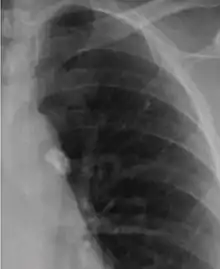

It is a small area of granulomatous inflammation, only detectable by chest X-ray if it calcifies or grows substantially (see tuberculosis radiology).[2] Typically these will heal, but in some cases, especially in immunosuppressed patients, it will progress to miliary tuberculosis (so named due to the granulomas resembling millet seeds on a chest X-ray).[2]

The classical location for primary infection is surrounding the lobar fissures, either in the upper part of the lower lobe or lower part of the upper lobe.[2]

If the Ghon focus also involves infection of adjacent lymphatics and hilar lymph nodes, it is known as the Ghon's complex or primary complex. When a Ghon's complex undergoes fibrosis and calcification it is called a Ranke complex.[2][3]